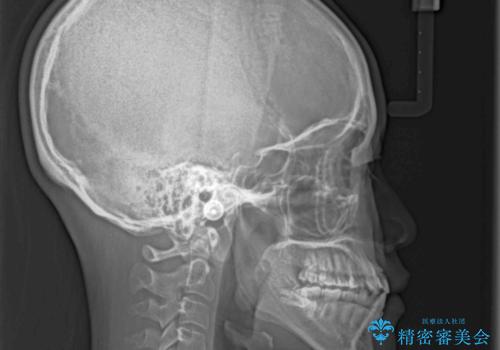

前歯のクロスバイトと変色した歯 ワイヤー矯正とセラミック治療

- 前歯のクロスバイトと神経を取り除いた後に変色してしまった前歯を気にして来院された患者様です。

ワイヤー矯正により矯正治療を行った後に、前歯の補綴治療を行うこととしました。

インビザラインでの矯正治療も十分に対応可能でしたが、自己管理の煩わしさから、ワイヤー矯正を行うこととしました。